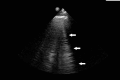

Lung ultrasound (LUS) is a dynamic, real-time, non-invasive bedside tool that offers increased sensitivity over standard imaging modalities in identifying pulmonary edema. This case highlights acute post-operative hypoxia secondary to pulmonary edema that was initially missed by chest radiography (CXR) and chest computed tomography (CT). The edema was diagnosed first on same day by bedside LUS, later seen on next day follow-up CXR and resolved with diuresis. LUS has demonstrated superior accuracy compared to CXR, but scant evidence compares it to CT. This case presentation serves to increase awareness of LUS as a highly sensitive and easy-to-use diagnostic tool for hospital providers in the evaluation of acute hypoxia.